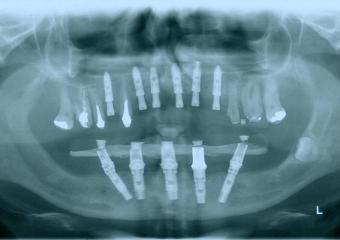

Raio - x com implantes inferiores em Junho de 2014  - Clínica Cliniface

Raio - x com implantes inferiores em Junho de 2014